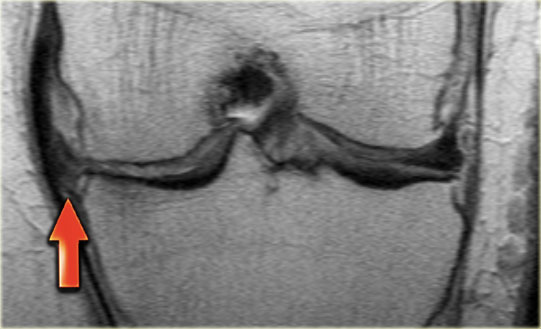

Rách sụn chêm vùng đỏ

Trước tiên, hãy cuộn qua các hình ảnh ở bên trái.

Hãy thử xác định tổn thương đang xảy ra với sụn chêm này.

Sau đó tiếp tục đọc.

Có một đường rách dọc ở ngoại vi của sụn chêm (mũi tên đỏ).

Một phần ba phía ngoài của sụn chêm được gọi là vùng ‘đỏ’, do có nguồn cung cấp máu phong phú.

Vị trí của đường rách sụn chêm có ý nghĩa quan trọng, vì các đường rách ở phần có mạch máu này có khả năng tự lành cao hơn so với các đường rách ở phần vô mạch hay vùng trắng của sụn chêm.